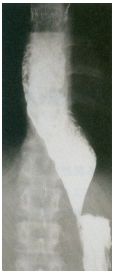

22. 37歲男性患者,主訴慢性腹痛一年以上,有止痛藥使用習慣,且最近有腹瀉、體重減輕現象,腹部超音波(圖1)及電腦斷層檢查結果(圖2),此患者可能出現下列的併發症(complication),除了 (A)黃疸 (B)胃腸出血 (C)維生素B1吸收不良 (D)葡萄糖耐受異常(impaired glucose tolerance) (E)皮下脂肪壞死(subcutaneous fat necrosis)